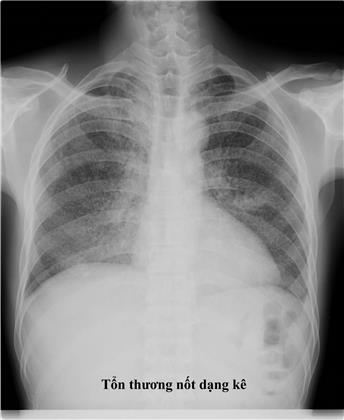

- Xquang phổi thường quy: hình ảnh trên phim X-quang gợi ý lao phổi tiến triển là thâm nhiễm, nốt, hang, có thể 1 bên hoặc 2 bên. Ở người có HIV, hình ảnh X-quang phổi ít thấy hình hang, hay gặp tổn thương tổ chức kẽ và có thể ở vùng thấp của phổi. X-quang phổi có giá trị sàng lọc cao với độ nhạy trên 90% với các trường hợp lao phổi AFB(+). Cần tăng cường sử dụng X-quang phổi tại các cơ sở y tế cho các trường hợp có triệu chứng hô hấp để sàng lọc lao phổi. Tuy nhiên cần lưu ý độ đặc hiệu không cao, nên không khẳng định chẩn đoán lao phổi chỉ bằng 1 phim X-quang phổi. Xquang phổi còn có tác dụng đánh giá đáp ứng với điều trị thử bằng kháng sinh thông thường trước khi chẩn đoán lao phổi không có bằng chứng vi khuẩn và để đánh giá kế quả điều trị lao sau 2 tháng và kết thúc điều trị.

Chẩn đoán xác định: lâm sàng: cấp tính với các triệu chứng ho, sốt cao, khó thở, có thể tím tái. X-quang phổi có nhiều nốt mờ, kích thước đều, đậm độ đều và phân bố khắp 2 phổi (3 đều: kích thước, mật độ và đậm độ cản quang các hạt kê trên phim X-quang phổi). Xét nghiệm đờm thường âm tính. Ngoài ra xét nghiệm vi khuẩn trong các mẫu bệnh phẩm (dịch phế quản, dịch não tủy, máu) có thể dương tính.